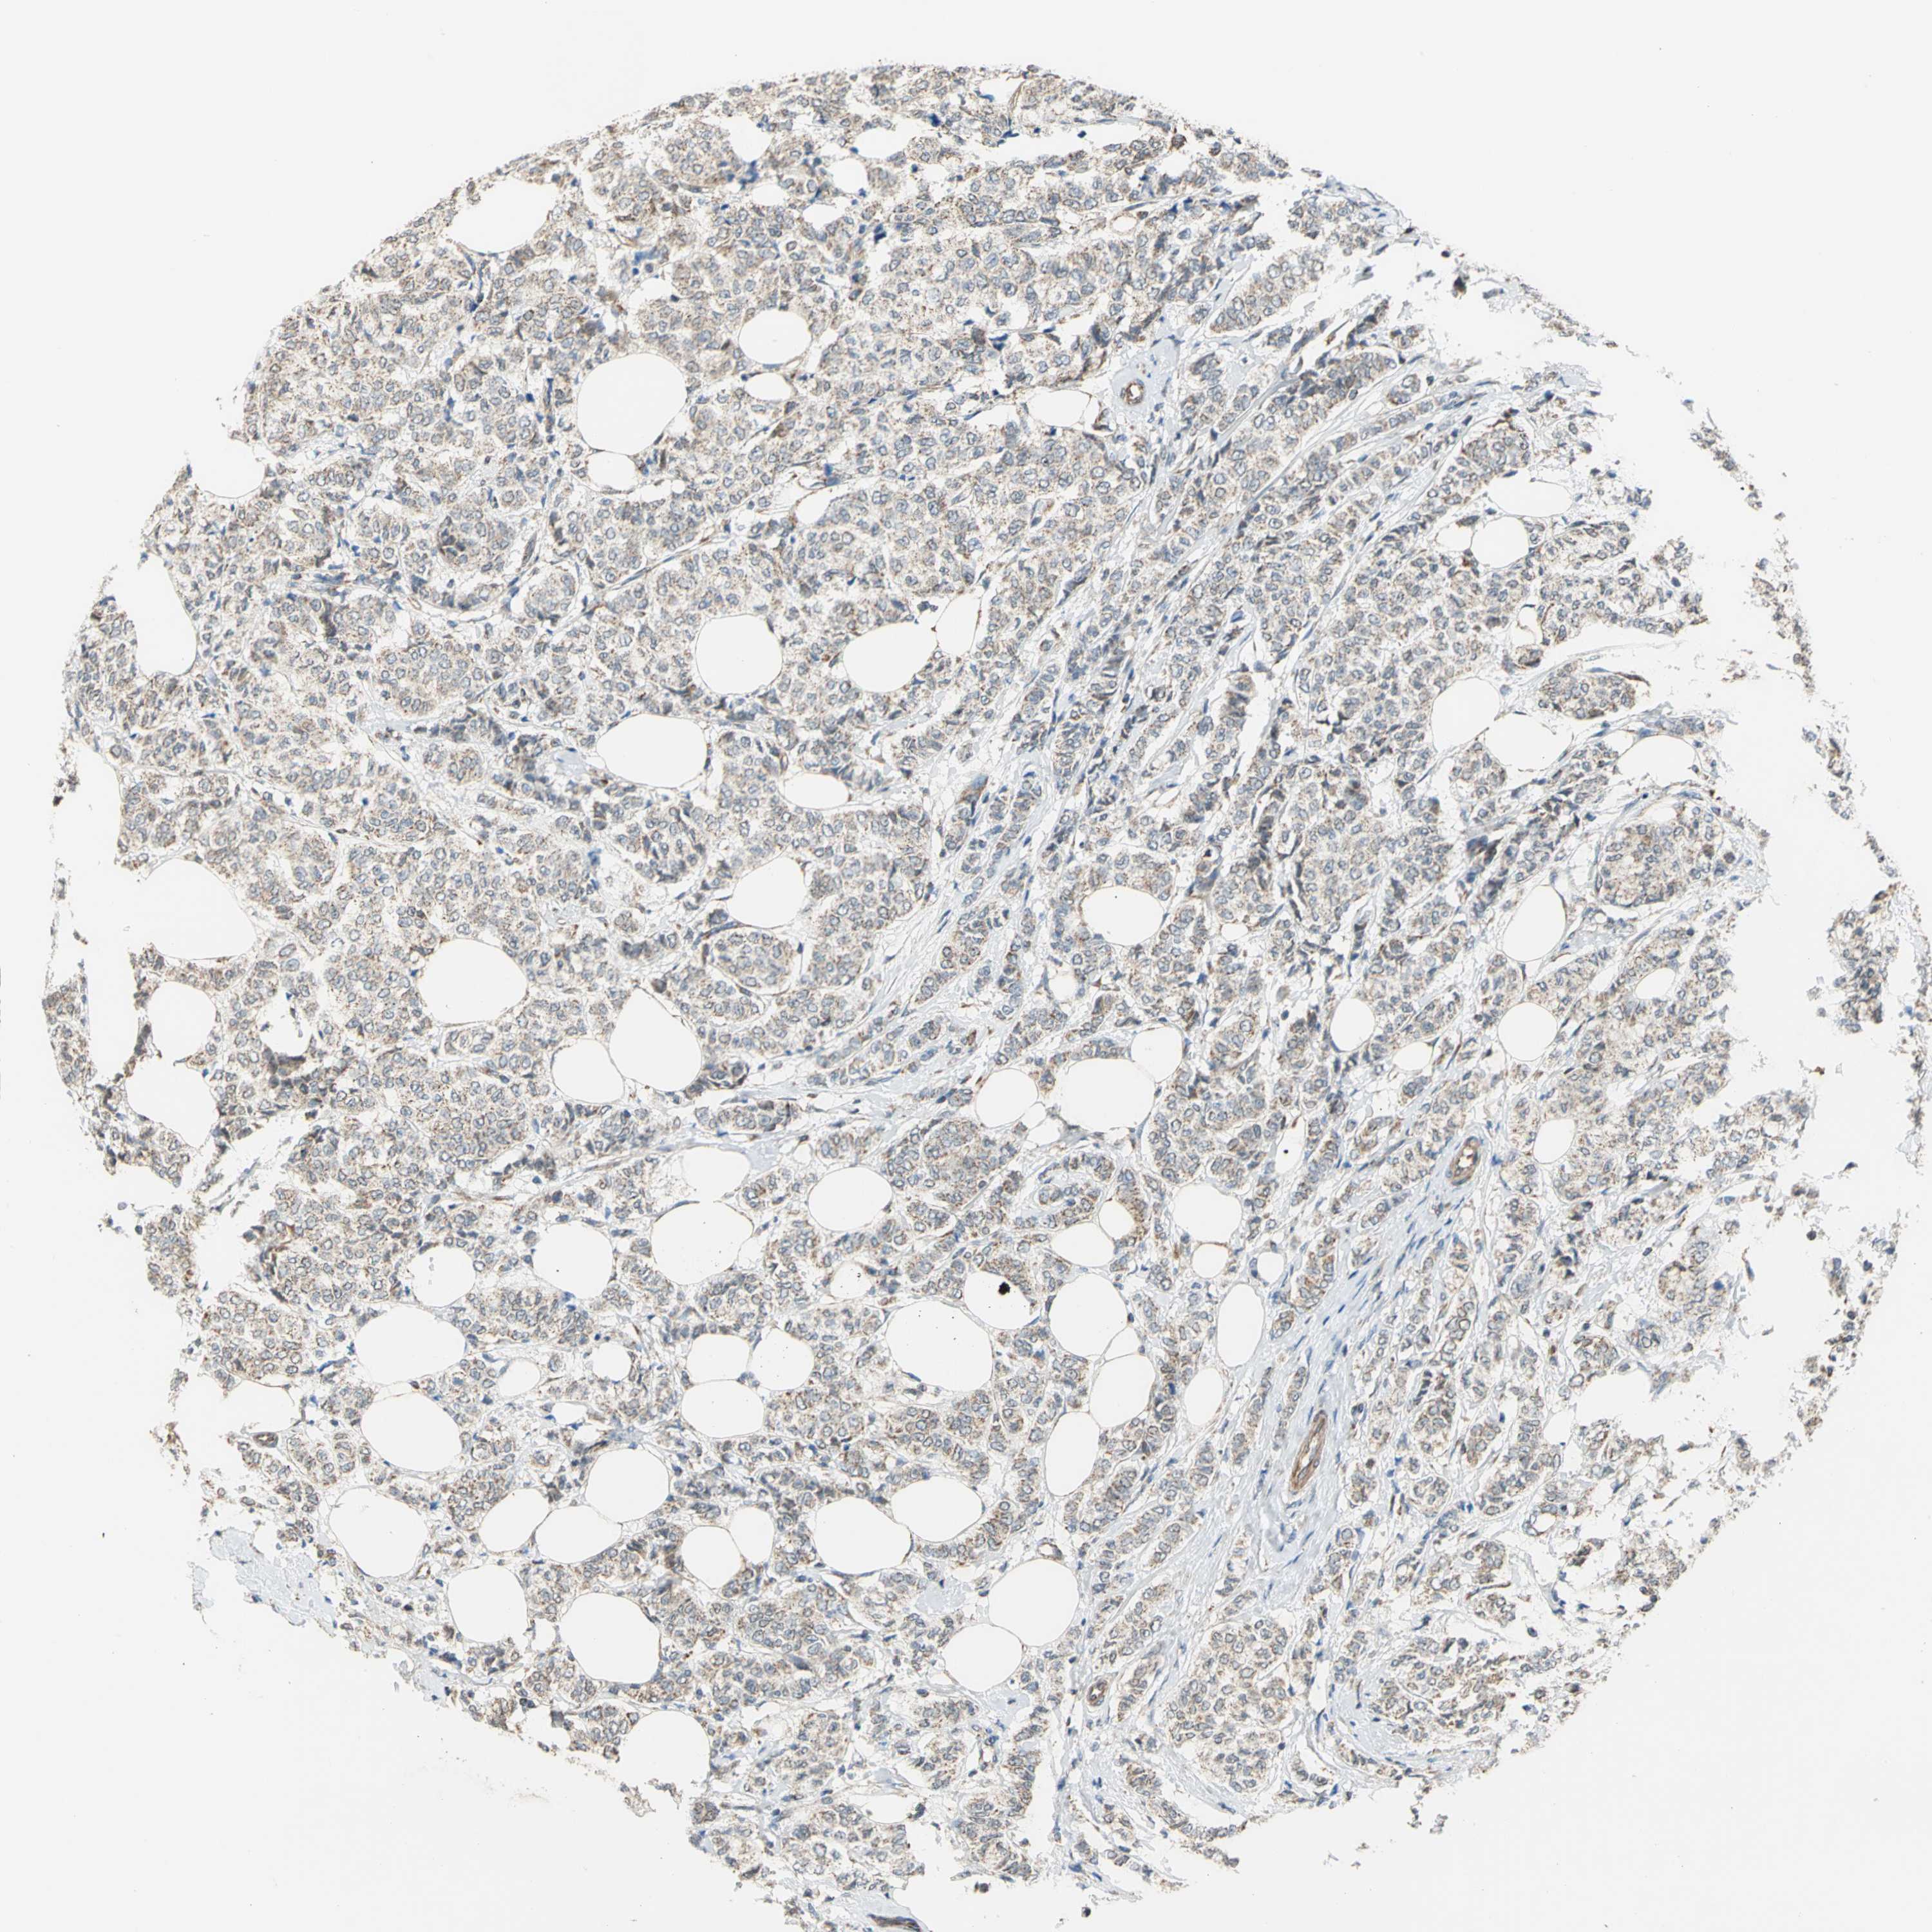

CANCER BREAST CANCER Show tissue menu

BRCA TCGA BRCA VALIDATION PROTEIN EXPRESSION